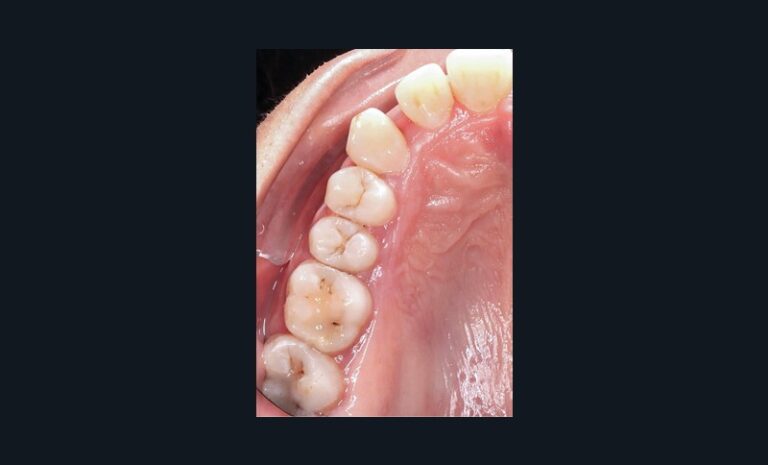

Dans l’exemple (fig. 1 et 2), la patiente présente une classe 1 molaire et classe 2 canine bilatérale sur un schéma normodivergent de classe 2 squelettique associé à une biproversion incisive et la canine 23 incluse.

Avec les aligneurs que je programme, la première phase de traitement consiste en un stripping de 0,5 mm de mésial molaire à distal canine afin de permettre une distalisation des prémolaires et canines pour obtenir un gain possible de 1,5 mm en mésial des canines avant l’étape d’alignement incisif.